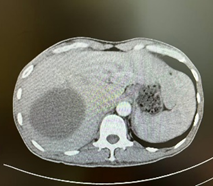

术前三维可视化分析

经术前三维成像评估右半肝切除后残肝体积为标准肝体积的50%,但吲哚箐绿(ICG)15分钟滞留率(ICG-R15)达25%,暂停手术,于是加强营养支持治疗,一周后复查ICG15分钟滞留率为14%,最后经肝胆胰外科专家组讨论不符合腹腔镜肝切除要求,决定行前入路右半肝切除术。右上腹斜切口进腹,探查见肝脏呈轻度肝硬化,两个肿瘤直径接近10.0cm的巨大肿瘤占据半肝,一个于包膜外可见,一个位于肝实质内,周围数个微小结节,未见肝内转移灶和腹腔转移灶,为避免术中不适当挤压引起肿瘤经血管转移和肿瘤破裂,先切断肝圆韧带和肝镰状韧带,解剖第二肝门,显露肝右和肝中静脉窝,然后切除胆囊,解剖第一肝门,鞘外分离右肝蒂,预阻断后见右肝缺血明显,除一个微小结节略偏向S4段外,肿瘤全部位于右肝缺血线内,于缺血性和S4段结节稍左侧约1.0cm画切肝线,术中超声证实肝中静脉位于切线下方、全部肿瘤位于切线右侧,结扎右肝蒂,以15+5min模式间歇性阻断肝门,原位离断左右肝之间肝实质,结扎切断肝断面血管和胆管,到达右肝蒂时确认右肝蒂后右切割闭合器离断右肝蒂,继续沿中肝静脉右侧离断肝实质,直至下腔静脉前壁,至此完全离断左右半肝之间的肝实质,然后于第三肝门显露、结扎、离断右侧肝短静脉,最后显露右肝静脉,切割闭合器离断右肝静脉,于Laennec膜外钝性分离肝裸区,离断右三角韧带和右冠状韧带,至此已原位肝切除术切除包括所有肝肿瘤的右半肝,移除切除物。肝癌切除术后余肝血运及回流良好,肝断面彻底止血后置橡胶引流管,关闭切口,术毕。